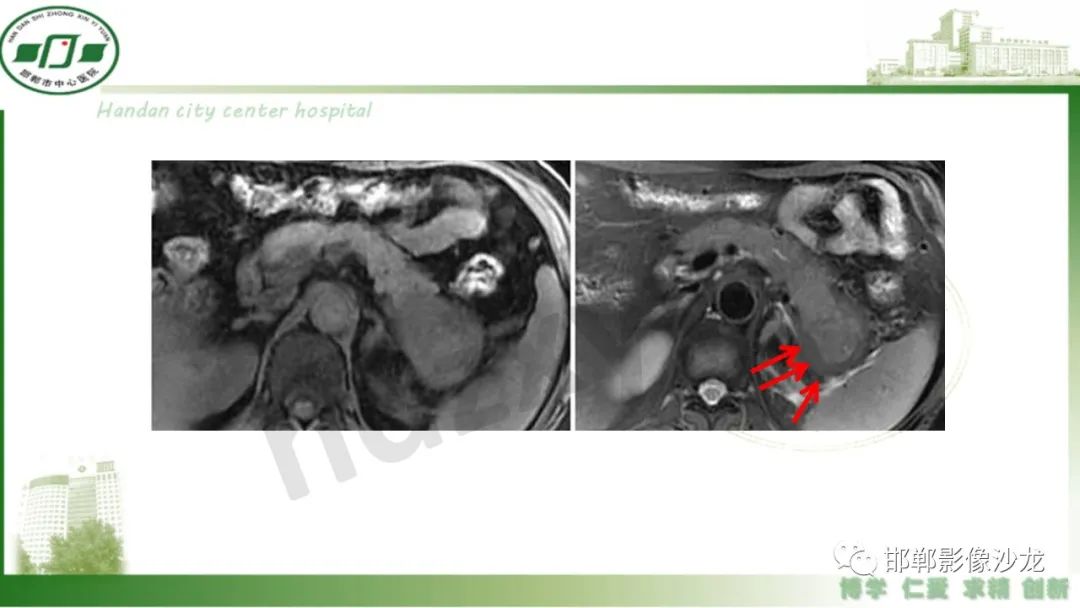

肿块性胰腺炎与胰腺癌的临床、实验室检查、影像学表现有时候很难鉴别,但两者的临床处理、预后又有很大的不同,因此我们平时工作中需要注意两者之间的区别,谨慎诊断,力争为患者及临床带来更大的帮助。